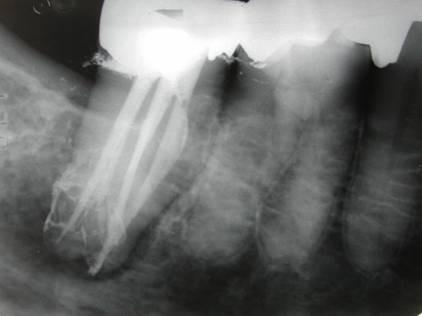

Pour cela il est bien insisté sur la préparation canalaire et les finitions aux inserts US, y compris l'ET20 D pour débrider assez profondément, mais sous loupes ou micro, ces anses si profondes de part et d'autre du canal principal, si admirablement illustrées par la radio post-op de Yana postée par al.

Merci al pour cet argument icônographique indiscutable!